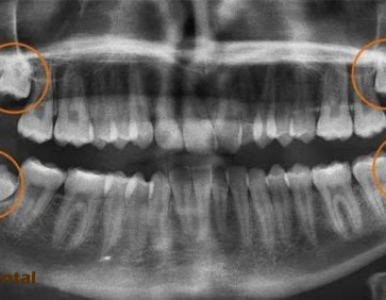

Răng khôn (răng số 8) thường mọc lệch, mọc kẹt gây đau, viêm nhiễm và nhiều biến chứng nguy hiểm. Cùng Nha Khoa SV tìm hiểu khi nào nên nhổ răng khôn an toàn.

Tìm hiểu dấu hiệu răng khôn mọc lệch, mức độ nguy hiểm và cách xử lý an toàn. Bài viết cung cấp thông tin đầy đủ, kèm video thực tế tại Nha Khoa SV.

Tìm hiểu răng số 8 (răng khôn), dấu hiệu mọc, các dạng nguy hiểm và phương pháp nhổ răng khôn chuẩn y khoa tại Nha Khoa SV.